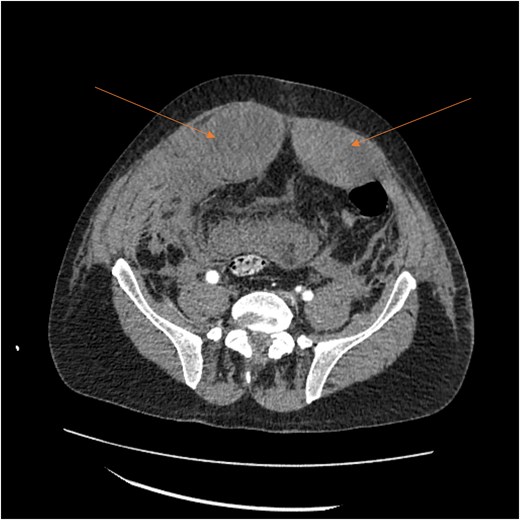

By hospital day 6, the patient’s condition improved. He was weaned from mechanical ventilation, his renal function improved (creatinine declined to 0.7 mg/dl), and hemoglobin stabilized at 8.4 gm/dl. The patient was clinically stable, and on hospital day 8, he was set up for discharge to a rehabilitation institution. However, on this day, he developed generalized abdominal pain associated with tachycardia, pulse = 118, and leukocytosis (white blood cells = 14.8 × 109/l). Physical exam revealed a distended abdomen with diffuse tenderness and sluggish intestinal sounds. A CT scan showed a large volume of pneumoperitoneum, minimal free fluid, and mildly dilated small bowel loops, consistent with a hollow viscus perforation with no identifiable source of perforation (Fig. 5) and a compression of rectosigmoid region against sacral promontory by the enlarged hematoma (Fig. 6). The right colon was decompressed compared with the prior study, and the RSH size remained unchanged, but there was progression of VTE burden. Prior to the acute deterioration, the patient had intermittently reported mild abdominal discomfort, which was initially attributed to the known RSH. There were no clinical signs suggestive of bowel obstruction, such as vomiting or significant abdominal distension. While the patient noted some degree of constipation, he reported that this was consistent with his baseline bowel habits and did not raise concern for new pathology.

CT scan demonstrating pneumo-peritoneum (arrow), indicative of a hollow viscus perforation.

CT scan demonstrating compression of large bowel (arrows) by the enlarged hematoma.